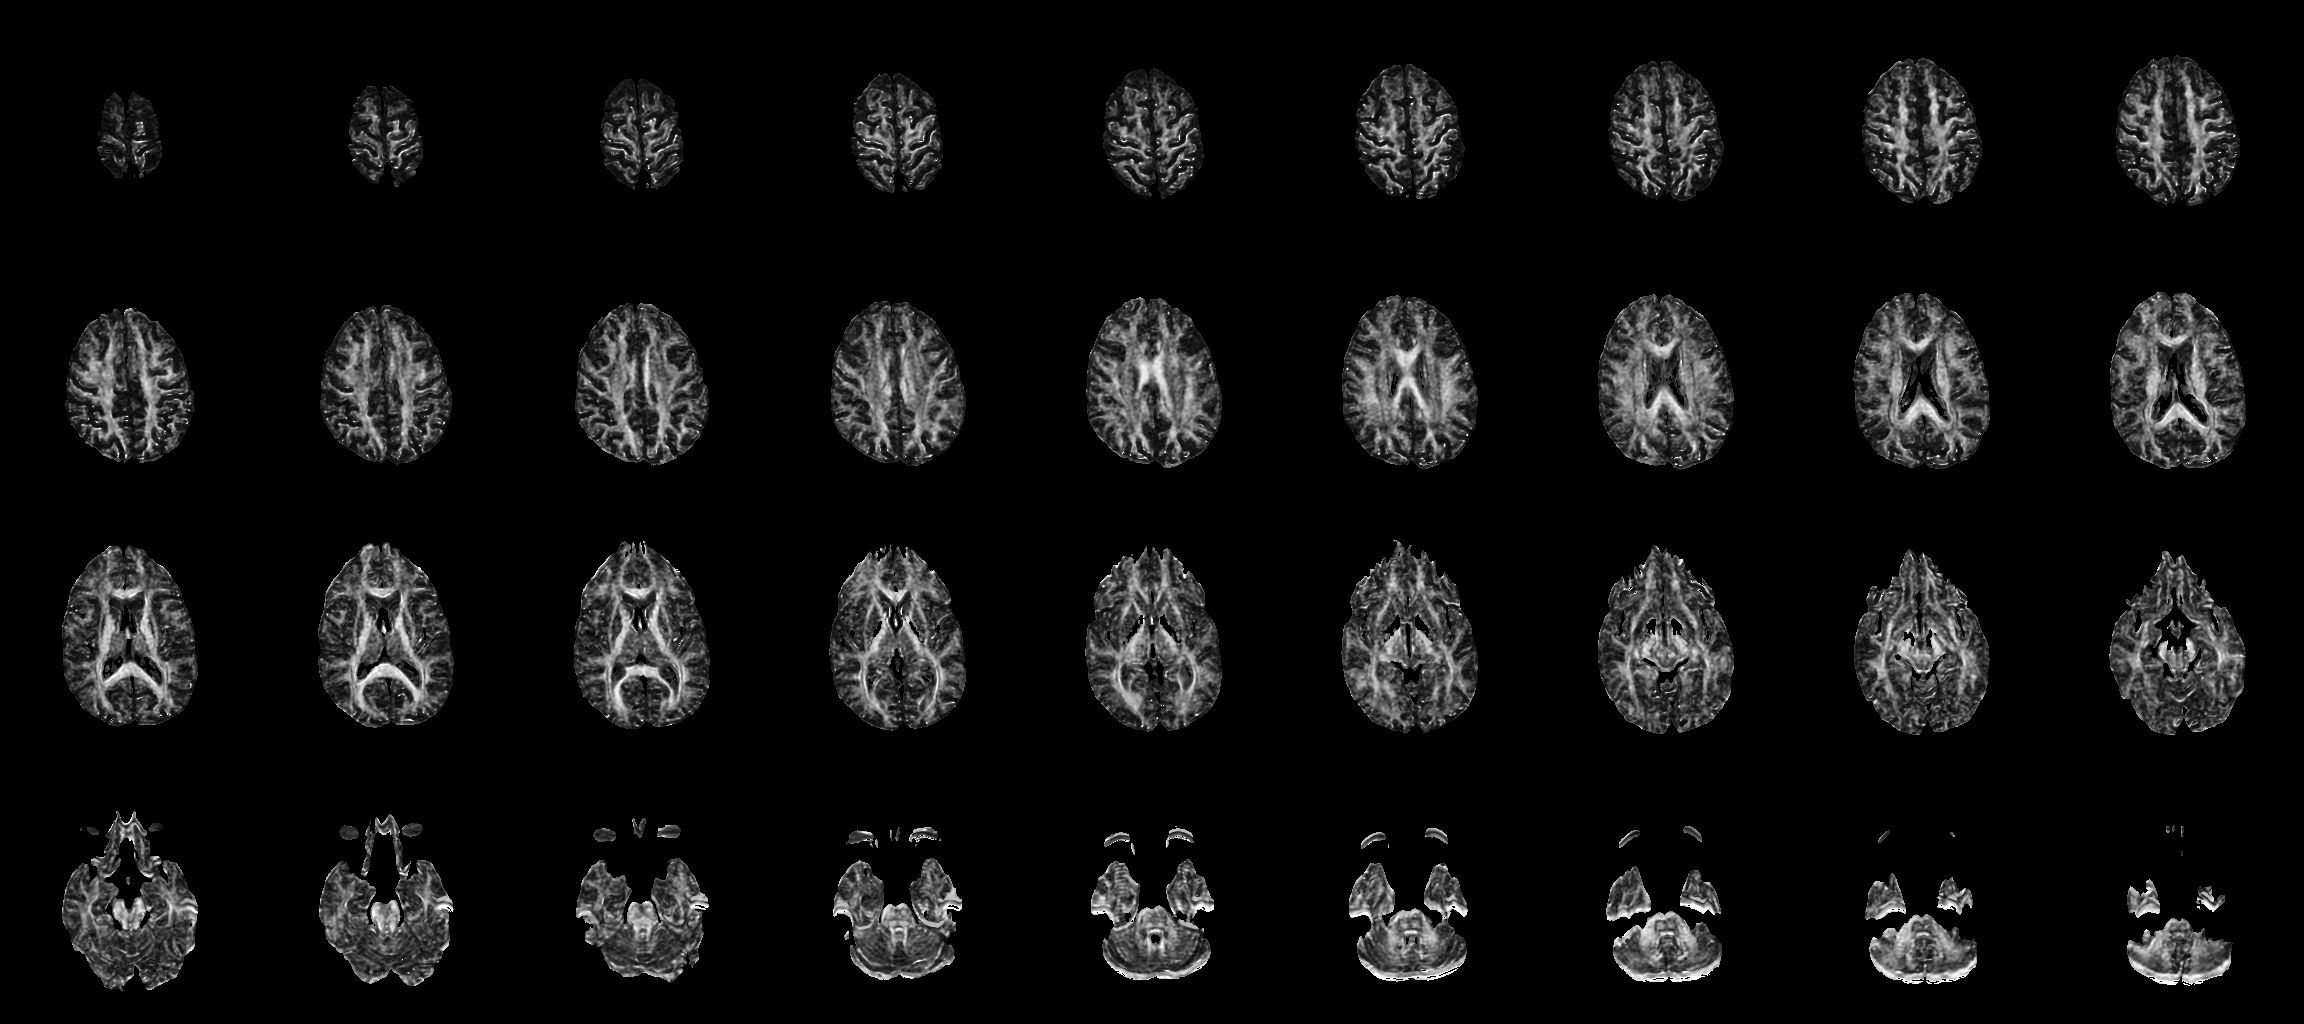

This crops out the B0 images, projects along the DWI images by measuring the standard deviation of the DWI values, tiles to a 9-by-4 image, quantizes and saves to PNG.

The fact that there is a lot of brightness above and below the brain is the sign of mis-registration: variance among the DWI implies anisotropy, and there should not be major anisotropy on the cortical surface.

This runs a http://www.sci.utah.edu/%7Egk/ismrm04/ on the DWIs, which models the shear/scale/translate distortion along the phase-encode direction as a linear function of the difffusion-sensitizing gradient that is creating the eddy currents that lead to imaging distortion. Then a new DWI stdv image is created like the first. The need to set the NRRD_STATE_KEYVALUEPAIRS_PROPAGATE environment variable is currently a bug, this will be fixed soon.

Like any registration method, the results can be improved by tuning the various parameter settings (type "tend epireg" for all the details); these are just the results from using mainly the defaults.